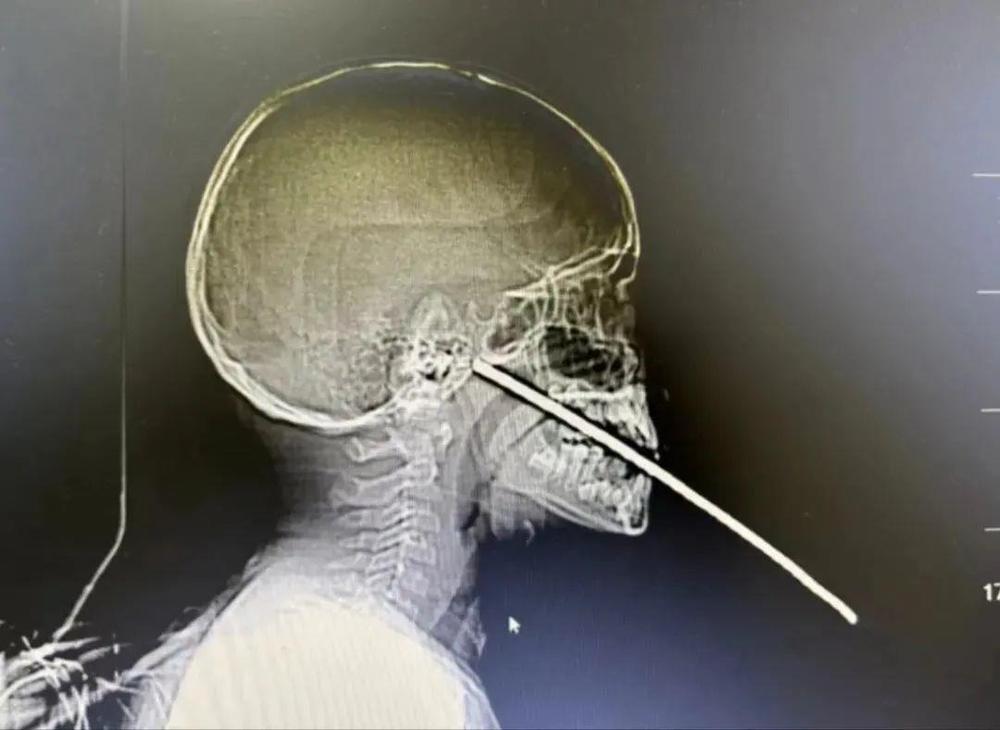

7月14日,云南省保山市一9岁男孩在玩耍时不慎摔倒,嘴巴被一根约1米长的钢筋插入,无法进行CT检查和后续治疗,医院急诊求助消防协助救治。

根据现场情况,1名消防员负责安抚小男孩,2名消防员在医生指导下利用断线钳将钢筋稳固,1名消防员则 利用钢筋速断器剪断钢筋。

经过10分钟的紧张救援,消防员成功将钢筋剪断,为医院下一步急救赢得了时间和条件。